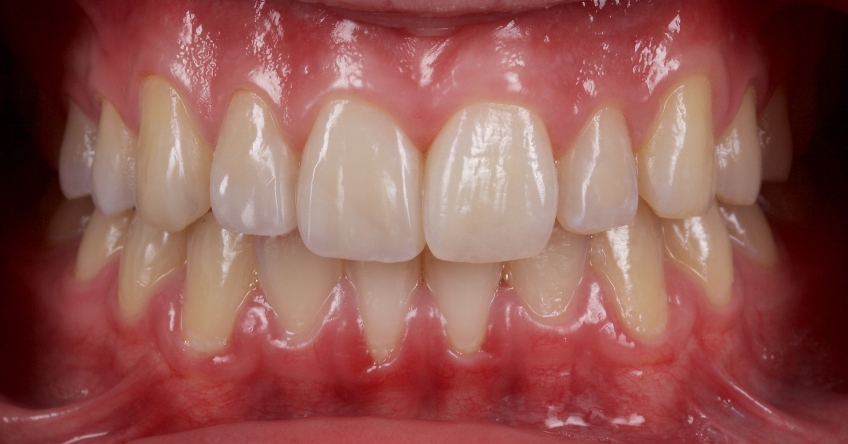

This 21-year-old male presented with an uncomplicated enamel-dentin fracture of the upper right central, lateral incisor, and canine following a fall.